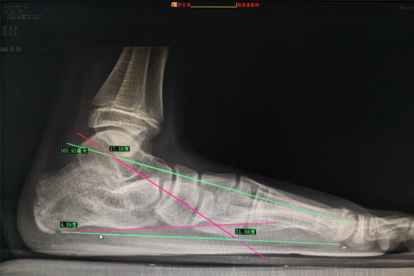

扁平足可能引发足部疼痛、步态异常、关节退变、脊柱侧弯及运动能力下降等问题。扁平足对身体的伤害主要有足弓支撑不足、足底筋膜炎、踝关节损伤、膝关节负荷增加、腰椎代偿性病变。